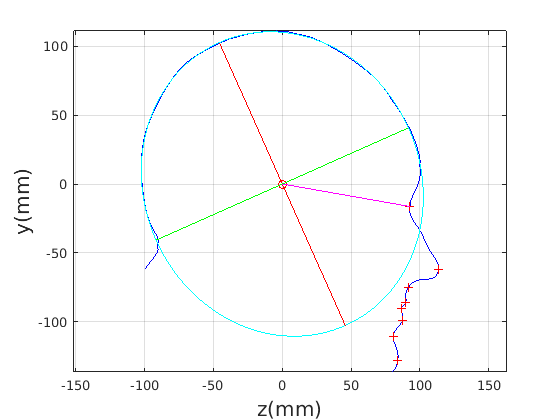

8 A case study of cranial profile model use for intervention outcome evaluation

In this section we take a sample of 25 boys, who are craniofacial craniosynostosis patients, 14 of which have undergone one type of corrective procedure (BS) and the other 11, another corrective procedure (TCR). Providing that the heads are sufficiently symmetrical and are amenable to ellipse fitting, we can parameterise all of these patients’ heads using our scale-normalised craniofacial profile model (2D model with face cropped out). We can then plot their pre-operative and post-operative parametrisations and compare them with the parameterisations of the 100 training examples. The expected result is that the parameterisations should show the head shapes moving nearer to the mean of the training examples. It also reveals which of the dominant modes of shape variation are most affected. The results are shown in figures 31 and 32.

For the BS patient set, the Mahalanobis distance of the mean pre-op parameters (red triangle in Fig. 31) is 4.670, and for the mean post-op parameters (blue triangle) is 2.302. For shape parameter 2 only these figures are 4.400 and 2.156.

For the TCR patient set, the Mahalanobis distance of the mean pre-op parameters (red triangle in Fig. 32) is 4.647, and for the mean post-op parameters (blue triangle) is 2.439. For shape parameter 2 only these figures are 4.354 and 2.439. We note that most of this change occurs in parameter 2, which corresponds to moving height in the cranium from the frontal part of the profile to the rear. In these figures we excluded one patient, who preoperatively already had a near-mean head shape (see red cross near to the origin in Fig. 32, so any operation is unlikely to improve on this (but intervention is required in order to relieve potentially damaging inter-cranial pressure).

It is not possible to make definitive statements relating to one method of intervention compared to another with these relatively small numbers of patients. However, the cranial profile model does show that both procedures on average, lead to a movement of head shape towards the mean of the training population. An example of analysis of intervention outcome for a BS patient is given in Fig. 33 and a TCR patient is given in Fig. 34. The particular example used is highlighted with circles on figures 31 and 32 to indicate pre-op and post-op parametrisations. To our knowledge this is the first use of statistical 3D craniofacial shape models in a clinical study.